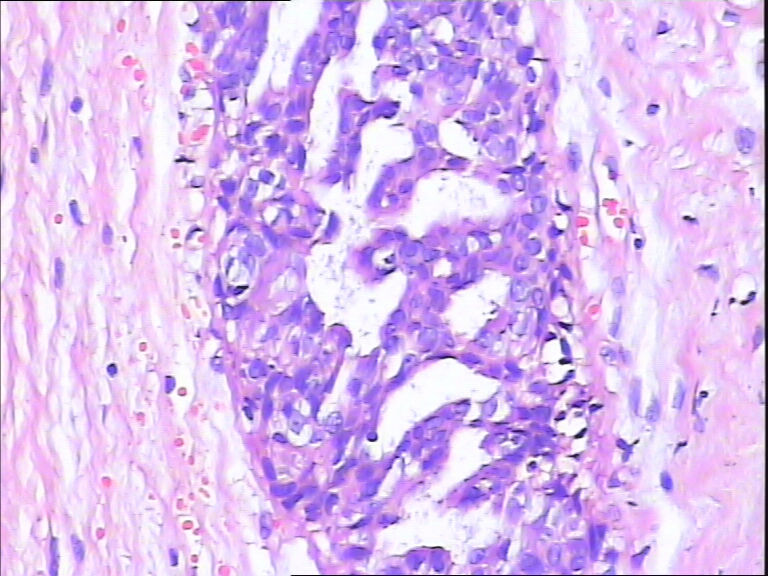

B3862乳腺包块

40岁,发现乳腺包快5月

标签:UDH ADH

导管内癌

标记CK5/6,CKH,P63

觉得不够癌

考虑导管内原位癌  需做组化确诊

ADH

DIN1b

觉得像UDH,做CK5,P63,UDH CK5腺上皮阳性,ADH CK5腺上皮阴性

Quality of the slides is not good.

More like UDH

导管不典型增生,不够导管内癌,做一做免疫组化就一目了然了

导管内原位癌  需做组化确诊

感觉不是普通型增生(UDH),应该到ADH或DCIS  免疫组化 ck5/6  34bE12